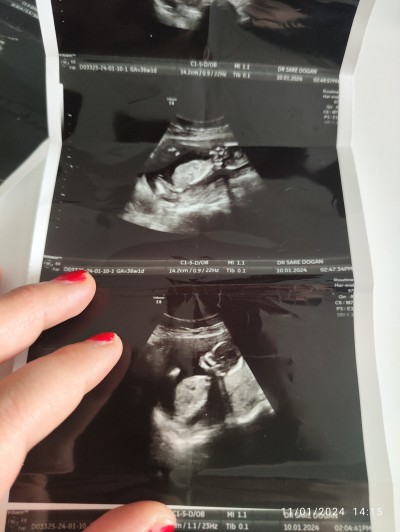

Anlayan var ise yorum yapabilir mi ilk gebelik hiç bişey anlamıyorum

Gebelik haftası 15+1